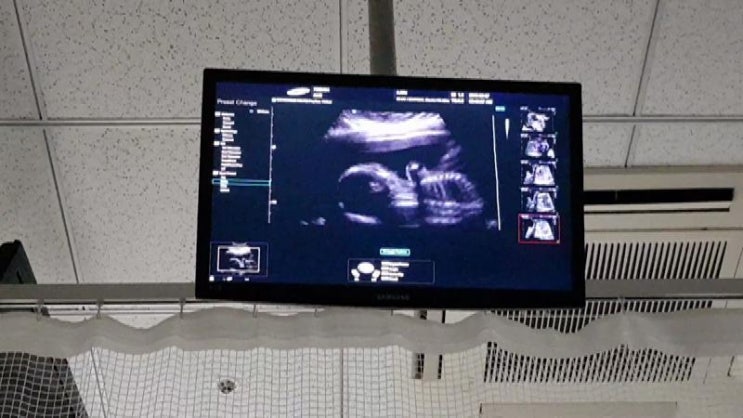

점점 더 사랑스러워지는구나 기록 : 2018. 3. 7 2018. 3. 7 만복 20주 1일이번에도 4주만에 만나고 온 우리...